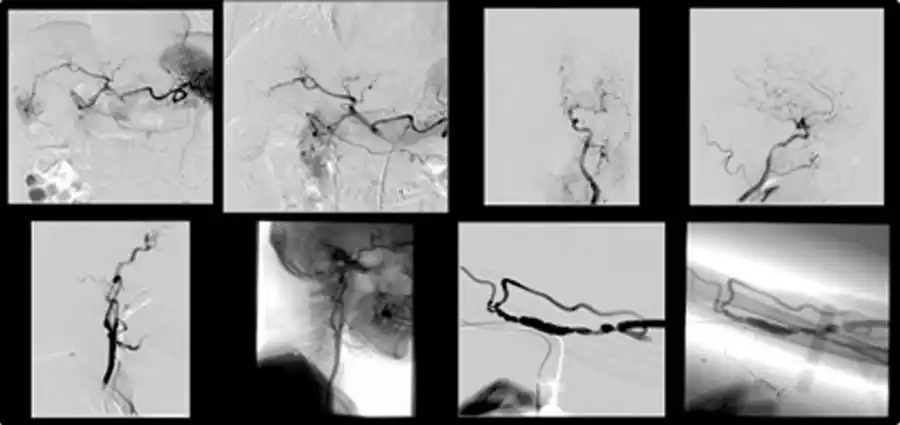

■DSA(多目的用血管撮影)

この装置では頭部・頚部・腹部等全身の血管を造影することができます。X線信号をデジタル化し造影剤注入前と注入後の画像を差し引きし血管のみが鮮明に描出され少ない造影剤で検査ができリアルタイムで撮影像が見られます。

脳血管造影や腹部血管造影やシャント静脈造影とそれらの塞栓術や拡張術を施行します。